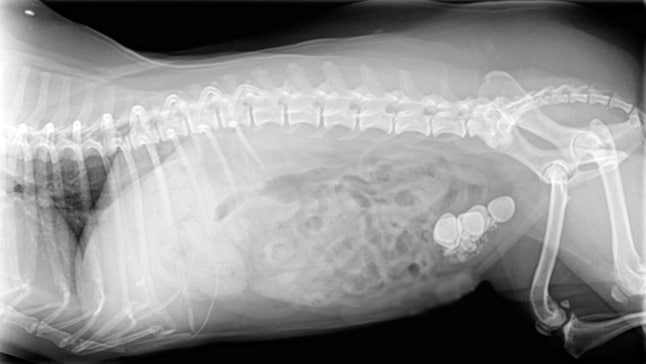

La acumulación y el endurecimiento de ciertas sales minerales en la orina es lo que provoca la formación de cálculos renales en los perros, un trastorno que puede perjudicar seriamente la salud de nuestros amigos…